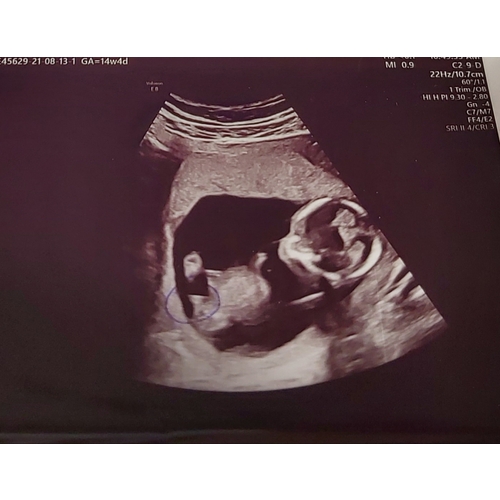

Maar op de eerste foto zijn de drie streepjes wel heel onduidelijk ik zal de mijne even erbij pakken..

Hier de 3 streepjes bij 15 weken en 3 dagen